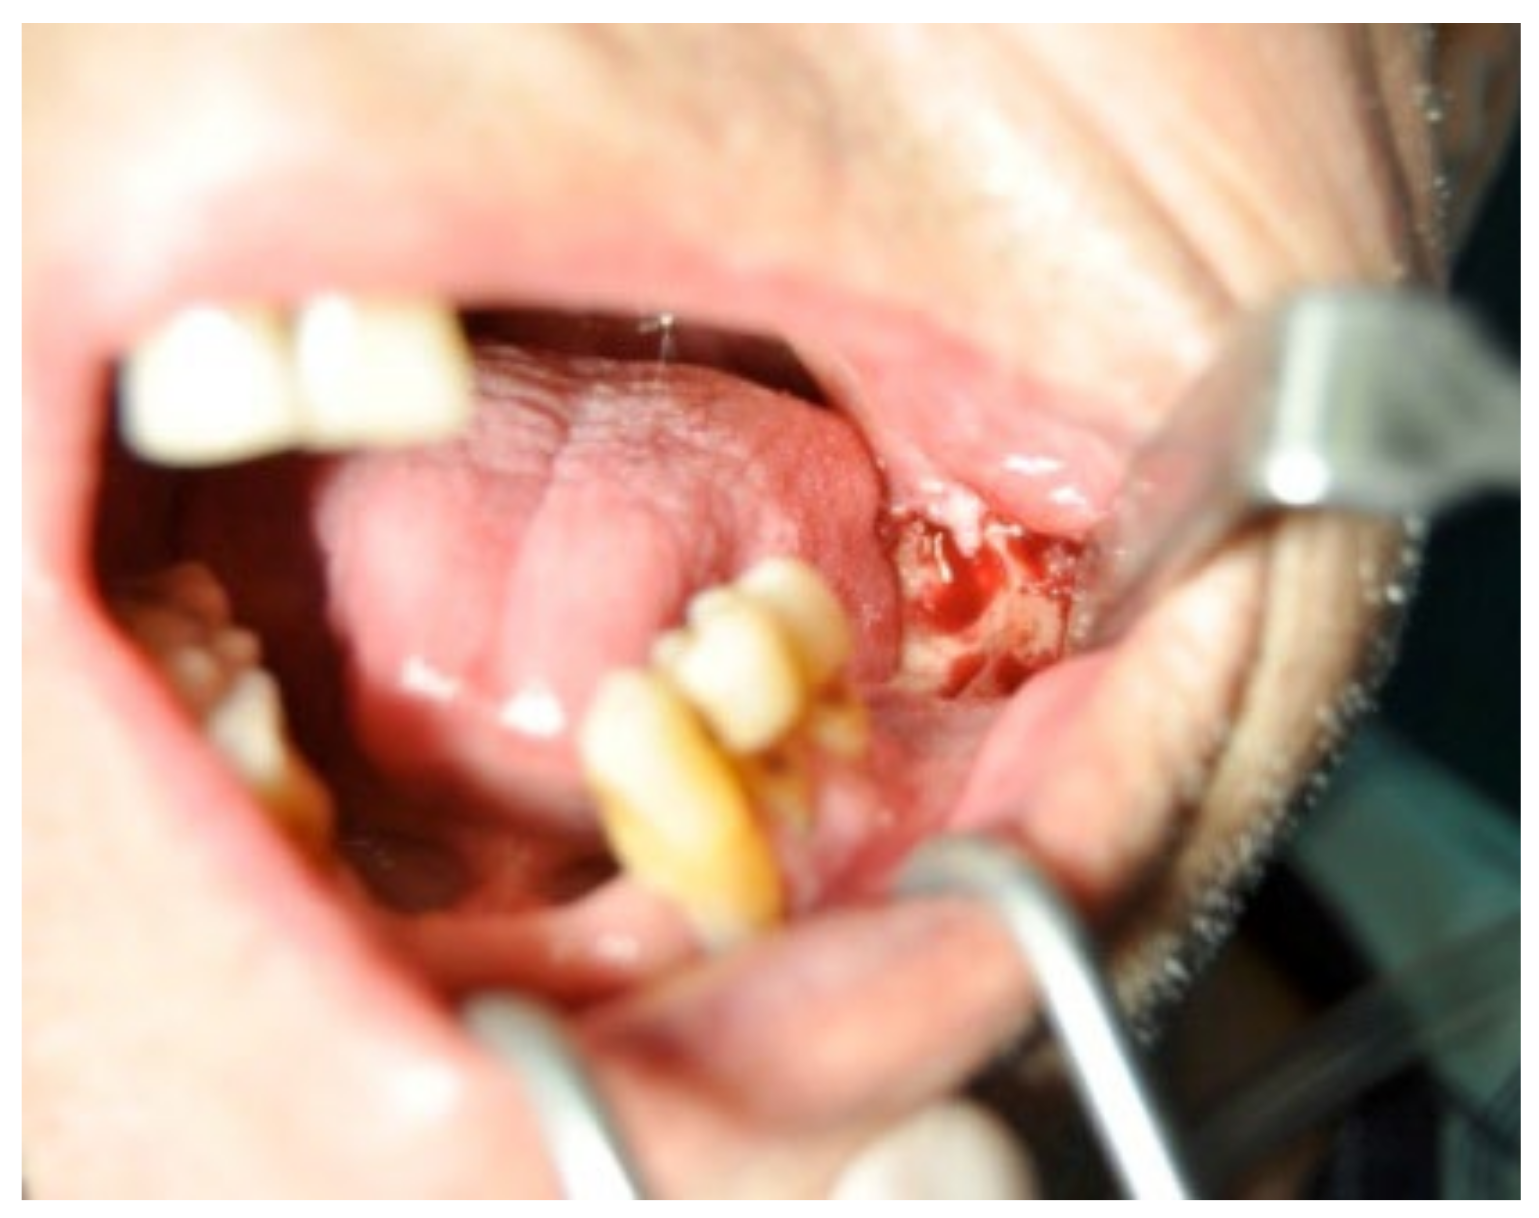

3.1. Clinical Case 1

3.2. Clinical Case 2

3.3. Clinical Case 3

3.4. Clinical Case 4

3.5. Clinical Case 5

3.6. Clinical Case 6